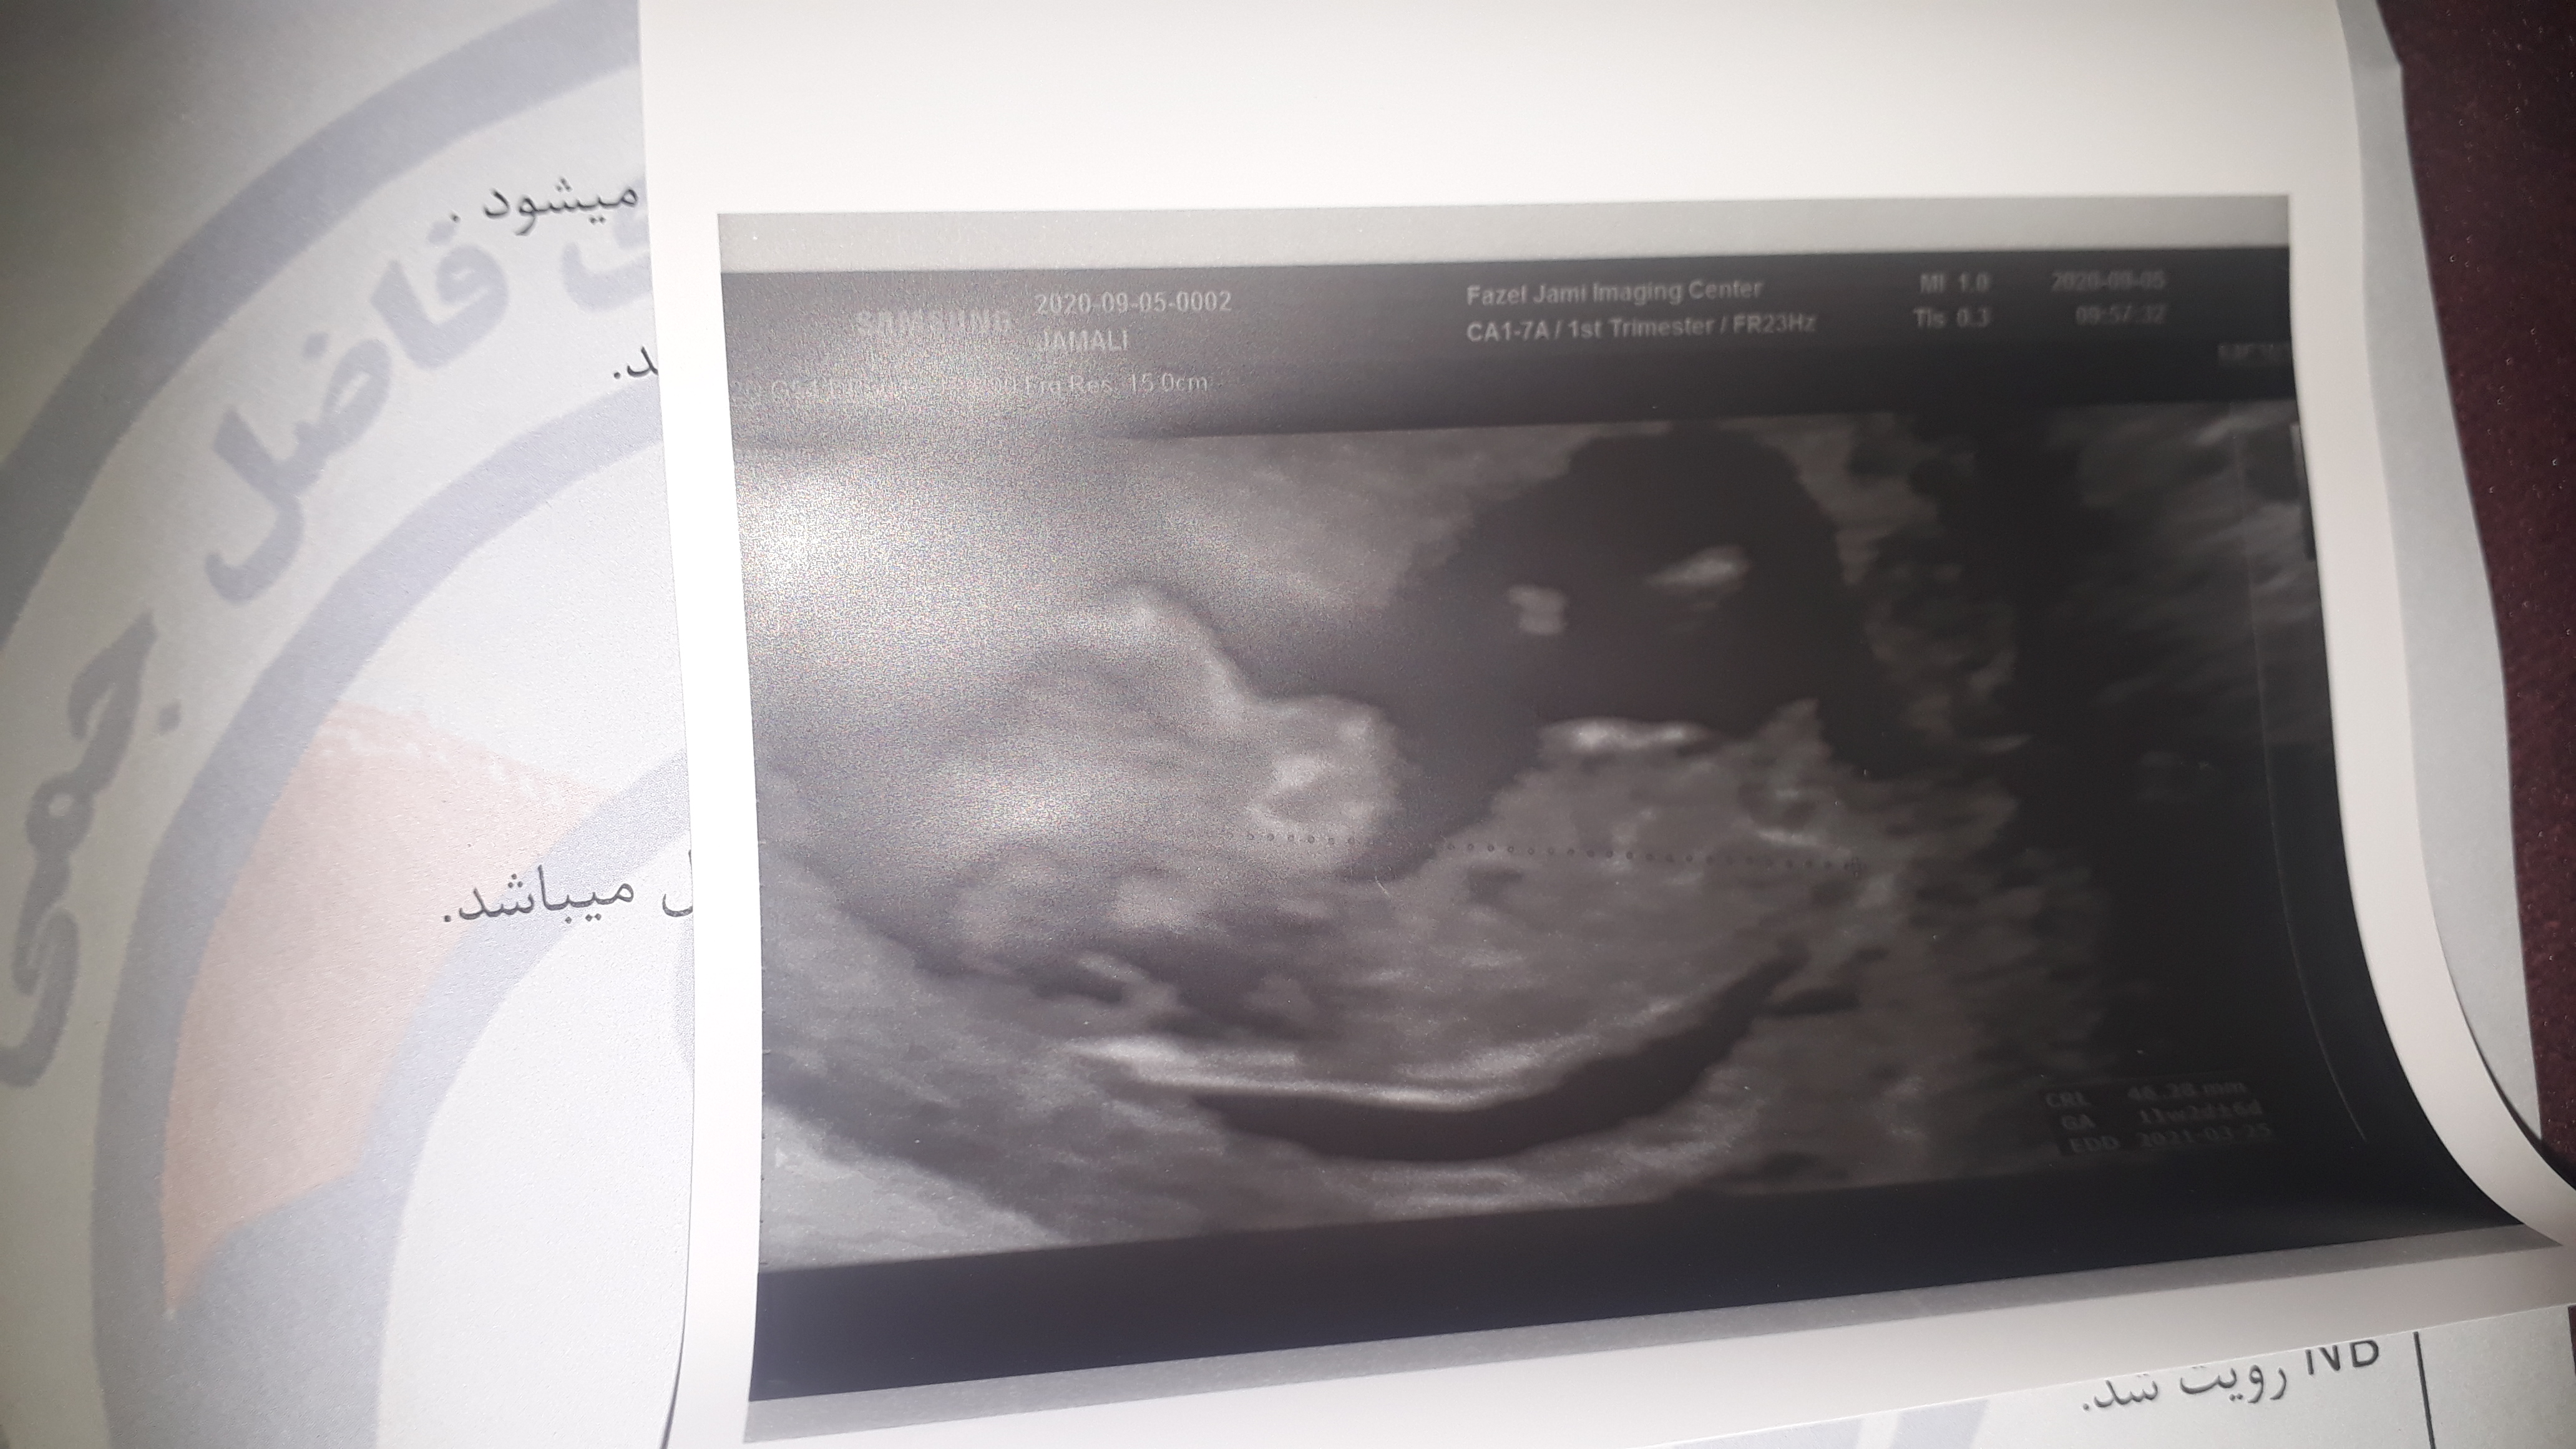

نی نی من ۸ هفته است می تونی حدس بزنی

پسرم منو بابایی و آجی دنیا بی صبرانه منتظر به دنیا اومدن و گرفتن دست های کوچولوت هستیم   خاله ها میشه برای سلامتی پسرم صلوات بفرستین

عزیزم ۸ هفته هنوز اندامشم تشکیل نشده گلم الان دنبال جنسیتش نباش